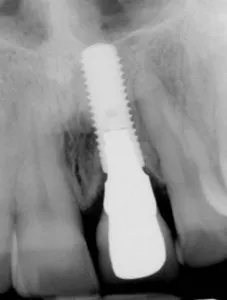

Antes y después de dos implantes de incisivos